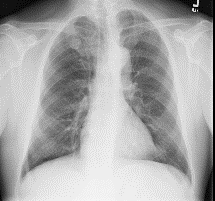

Among various medical imaging tools, chest radiographs are the most important and widely used diagnostic tool for detection of thoracic pathologies. Research is being carried out in order to propose robust automatic diagnostic tool for detection of pathologies from chest radiographs. Artificial Intelligence techniques especially deep learning methodologies have found to be giving promising results in automating the field of medicine. Lot of research has been done for automatic and fast detection of pneumothorax from chest radiographs while proposing several frameworks based on artificial intelligence and machine learning techniques. This study summarizes the existing literature for the automatic detection of pneumothorax from chest x-rays along with describing the available chest radiographs datasets. The comparative analysis of the literature is also provided in terms of goodness. Limitations of the existing literature along with the research gaps is also given for further investigation. The paper provides a brief overview of the present work for pneumothorax detection for helping the researchers in selection of optimal approach for future research.